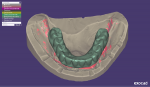

For the digital impression, scan bodies were tightened onto the multi-unit abutments and an intraoral digital impression was made using an IOS system (TRIOS). Subsequently, the conversion prosthesis was delivered to the patient with postoperative instructions on how to clean it and maintain a soft diet for the next 8 weeks. A second intraoral digital impression of the conversion prosthesis was made using the same IOS system (TRIOS). The STL files from intraoral scanning of the implants and the conversion prosthesis were also saved (Figure 6).

The previously generated STL files from conventional and digital impressions were imported into a CAD software (Exocad® DentalCAD, Exocad, exocad.com), and the files were made to overlap each other (Figure 7).10-12 Virtual cutback was performed with the CAD software to create a screw-retained framework with individual abutment preparations for multiple single crowns in a digital workflow. This virtually designed framework was sent to a CAM facility (NobelProcera®, Nobel Biocare), where the definitive framework was milled from titanium block.